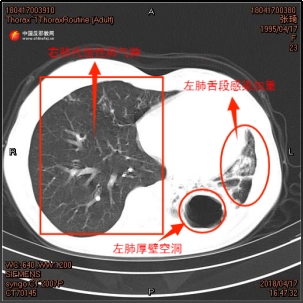

During her second tuberculosis diagnosis in April 2018, sputum cultures confirmed a co-infection of Aspergillus fumigatus. Dr. Zhang Yang, her resident physician at the time, recalled the challenges of her treatment, "Zhang Qi’s second diagnosis was relapsed multi-drug-resistant tuberculosis (MDR-TB). We developed a targeted treatment plan and added oral antifungal medication." Chest CT scans taken over the course of her treatment documented the deterioration of her left lung, the cavitation in the lower lobe of the left lung was expanding, the lung lobe was atrophying, and the infection was progressively worsening.

▲ Left: Chest CT scan of Zhang Qi from April 2017; Right: Chest CT scan from April 2018.